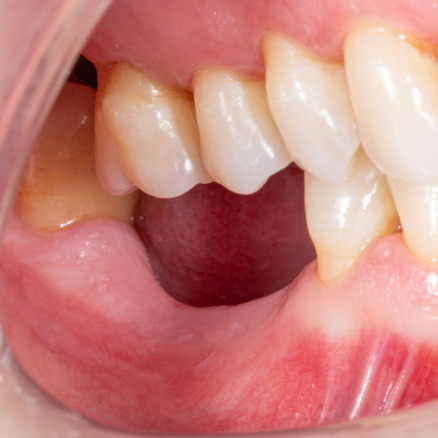

Ana sayfa > Klinik Vakalar > Diş çekiminin yıllar önce yapılmış olmasına bağlı olarak ince kemik varlığında implant ve kemik grefti uygulandı

Diş çekiminin yıllar önce yapılmış olmasına bağlı olarak ince kemik varlığında implant ve kemik grefti uygulandı